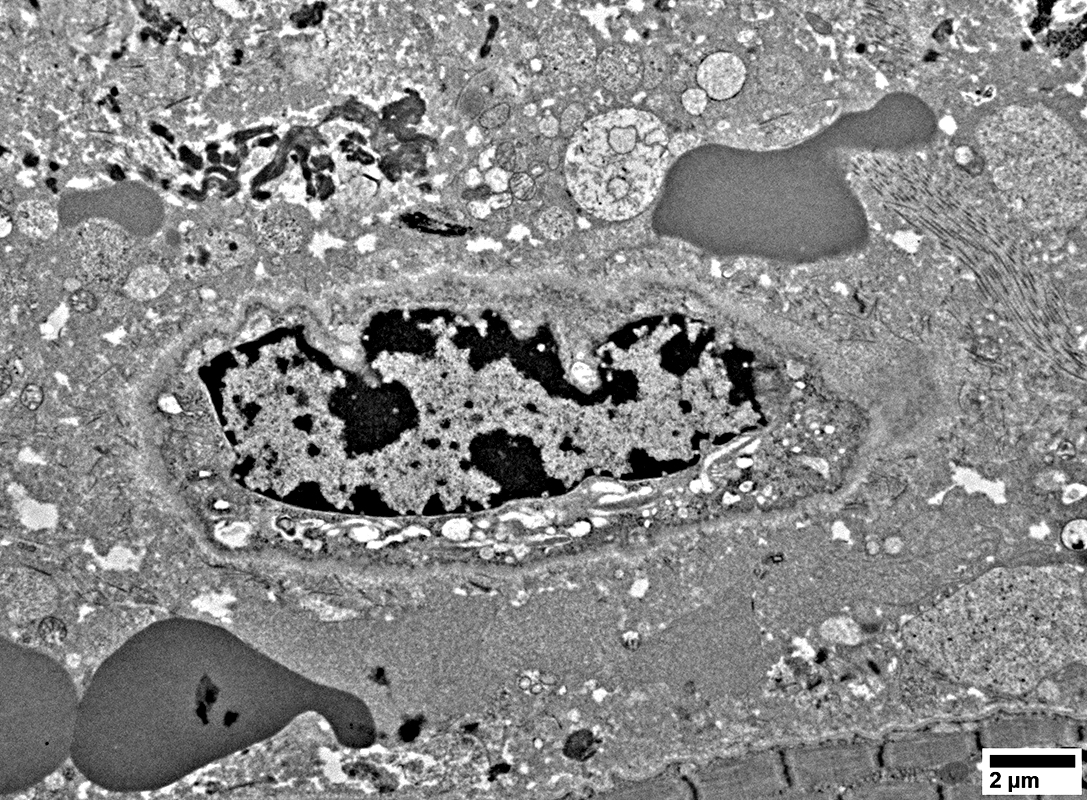

Damaged Capillary

No lumen

Endothelial cell with cytoplasmic vesicles inside a basal lamina

Erythrocytes & Vesicles in Endomysium

From: R Schmidt